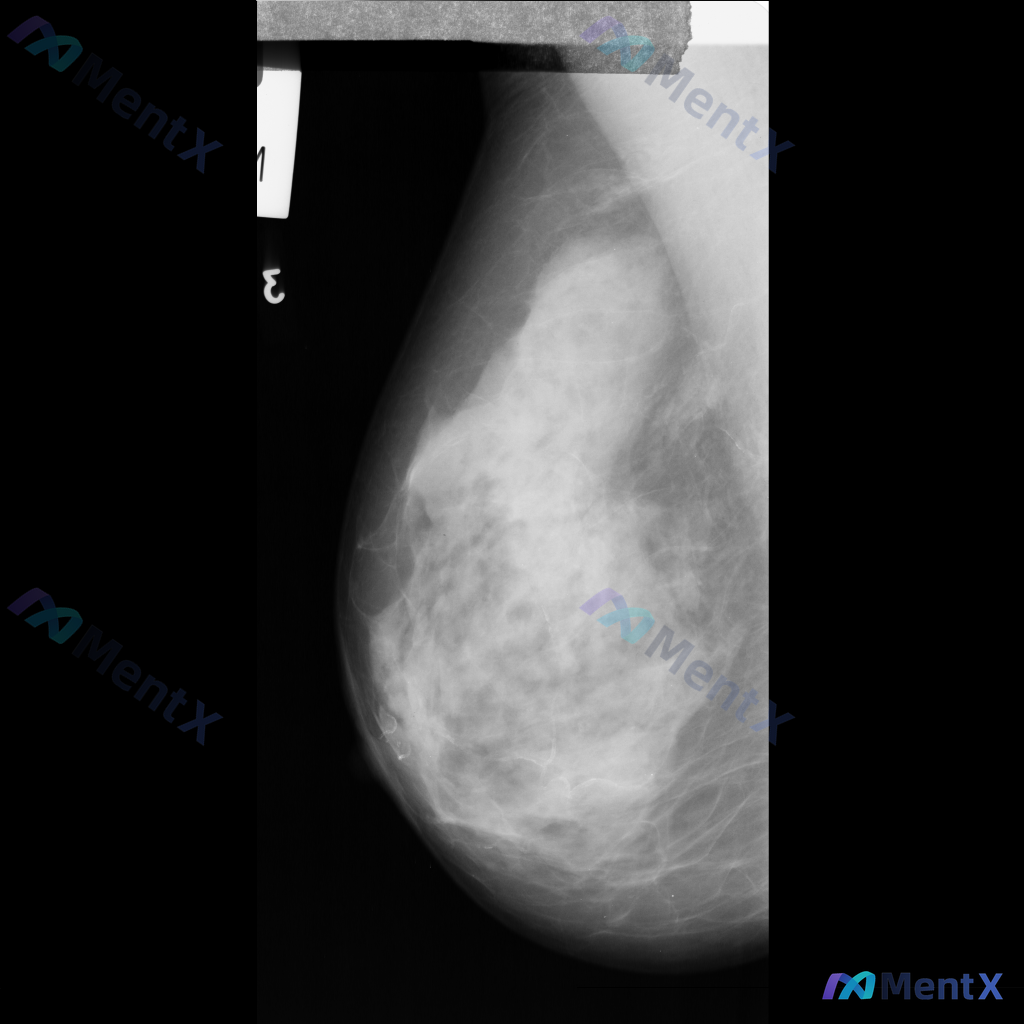

整理到一组乳腺钼靶的影像资料,大家先一起看看: 影像表现: - 病灶位于乳腺上中部(大致外上象限)可见一局限性高密度肿块影 - 形态不规则,边缘有毛刺状改变 - 周围腺体结构有扭曲、牵拉征象 - 肿块内部或附近可见点状钙化,部分呈簇状分布 目前只有这组钼靶表现,大家先不补充更多临床信息的话,大家更倾...